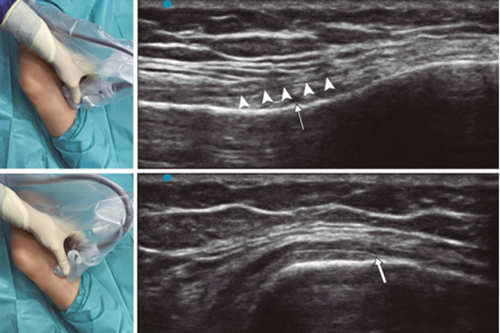

Ultrasound-guided genicular nerve radiofrequency

Fig. 3. Sonoanatomy and technique for performing superior medial genicular nerve block (SMGN). The transducer is located on the distal long axis of the femur and once the position of the SMGN (asterisks) is known, the probe is rotated 90 degrees to obtain a view of the femur short-axis (don't forget to keep the same depth that we find the SMGN on the long axis). VM (vastus medialis).

In order to achieve a correct location of anatomical landmarks by ultrasound we must place the patient in supine position with the knee flexed and a pillow under the popliteal fossa (14,16,19).

Fig. 4. Sonoanatomy and technique for performing inferior medial genicular nerve block (IMGN). The transducer is located on the proximal long axis of the tibia and we identify the vasculonervious package of the IMGN (arrow) just below medial collateral ligament (arrowheads). Then the probe is rotated 90 degrees to obtain a short-axis view of the tibia (don't forget to keep the same depth as the IMGN found on the long axis).

After performing knee asepsis/antisepsis, surgical field placement, and the sterile sheath of the high frequency linear transducer, we proceed to locate the SMGN (Figure 3). Placing the probe in a coronal plane on the inner face of the knee, we slide it cranially to visualize the junction of the metaphysis to the femoral diaphysis and the superior medial genicular artery/nerve (ASMGN), usually located near the periostium of the femur (if this neurovascular structure is not found, the junction between metaphysis and femoral diaphysis is taken as a reference). The mid-point of the transducer corresponding to ASMGN is then marked on the skin and the transducer is rotated to be placed in the transverse or axial plane to view ASMGN on the short axis (if this structure is not visible, confirm that we are at 50 % depth of the femur). In this cross-section the needle of the TRF is advanced in plane from anterior to posterior toward the ASMGN or to a depth of 50 % of the thickness of the femur. Finally, the transducer is rotated 90° again, leaving it in a coronal plane to check that the needle tip is near the ASMGN or the junction of the metaphysis and femoral diaphysis (14,16,19).

To locate the IMGN (Figure 4), we placed the transducer in a coronal plane on the inner face of the knee, sliding it caudally to identify the diaphysis junction with the tibial metaphysis and the inferomedial genicular artery/nerve (AIMGN). And we repeat the same steps we used for SMGN. If the AIMGN is not found, the reference to be taken shall be the depth of 50 % of the thickness of the tibia (14,16,19).

To locate the SLGN, the patient must be supine with the lower limb in internal rotation, obtaining good exposure to the lateral side of the thigh. We place the linear transducer in a coronal plane on the lateral side of the knee, slide it in a cranial direction to visualize the junction of the metaphysis with the femoral diaphysis and the superior lateral genicular artery/nerve (ASLGN), and repeat the same steps that we use for SMGN (14,16,19).